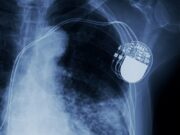

In addition to catheter guidewires, pacemaker leads also rely on high-quality medical wire. For this application, Sandvik offers wire with ultra-high strength and ductility, as well as excellent corrosion resistance.

“The tried and trusted method of cardiac pacemakers is still a wire-based system,” Davis explains. “There are wires that are used to conduct energy coming from a battery pack that’s located just under the skin. That electrical energy is conveyed through wires comprising part of the cardiac pacemaker lead system to stimulate the heart to make sure that it’s beating and maintaining a steady rhythm.

This means than pacing leads are subject to a great deal of cyclic fatigue and require excellent conductive qualities. There is usually a lot of redundancy with pacemaker leads in case there is a breakage and another wire needs to take over, so the electrical energy of these different leads is kept separate using a dielectric coating. Having high dielectric strength is also a safeguard against the pacemaker device from shorting. The EXERA® branded wires deliver excellent fatigue and relaxation resistance, as well as insulating polymer coatings.